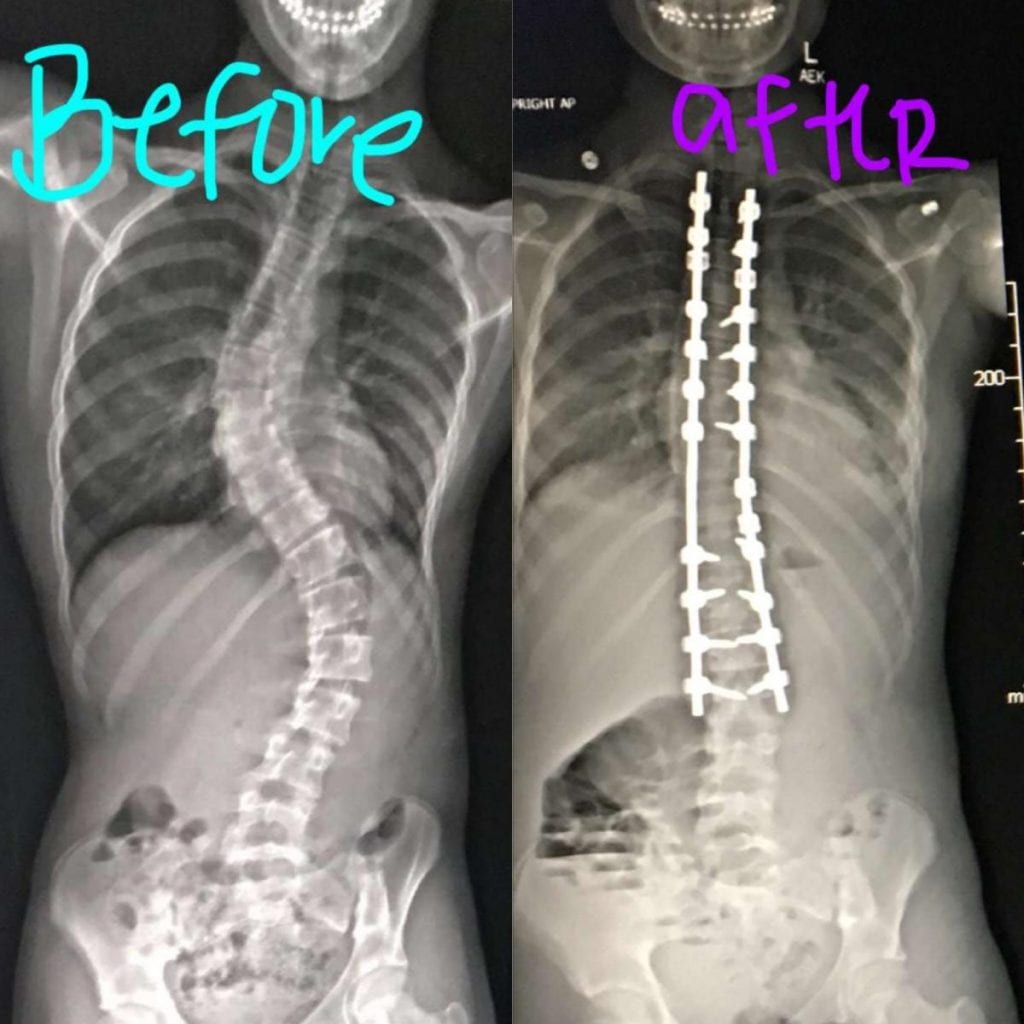

Scoliosis X Ray With Rods Scoliosis Metal Rod Surgery Cost In adolescent idiopathic scoliosis, the primary surgery used today is fusion surgery. Scoliosis surgery, also known as spinal fusion surgery, is performed to correct curvature of the spine of more than 25 to 30 degrees. In this surgery, metal implants are attached to the spine and then connected to a single rod or 2 rods. A surgeon will insert metal. Scoliosis Metal Rod Surgery Cost.

Before and After Scoliosis Surgery with Darryl Antonacci Scoliosis Metal Rod Surgery Cost A person may have an. Scoliosis surgery, also known as spinal fusion surgery, is performed to correct curvature of the spine of more than 25 to 30 degrees. The harrington rod is a metal rod that is commonly used in scoliosis surgeries performed in the united states. It's usually recommended for people with. In this surgery, metal implants are attached. Scoliosis Metal Rod Surgery Cost.

Scoliosis XRay before/after; 28 titanium screws + 2 cobalt chrome rods Scoliosis Metal Rod Surgery Cost Scoliosis surgery, also known as spinal fusion surgery, is performed to correct curvature of the spine of more than 25 to 30 degrees. There are several types of metal rods used in scoliosis surgery, each with its own advantages and considerations. In this surgery, metal implants are attached to the spine and then connected to a single rod or 2. Scoliosis Metal Rod Surgery Cost.

Scoliosis X Ray Before And After vrogue.co Scoliosis Metal Rod Surgery Cost In adolescent idiopathic scoliosis, the primary surgery used today is fusion surgery. Scoliosis surgery, also known as spinal fusion surgery, is performed to correct curvature of the spine of more than 25 to 30 degrees. There are several types of metal rods used in scoliosis surgery, each with its own advantages and considerations. There are a lot of variables that. Scoliosis Metal Rod Surgery Cost.